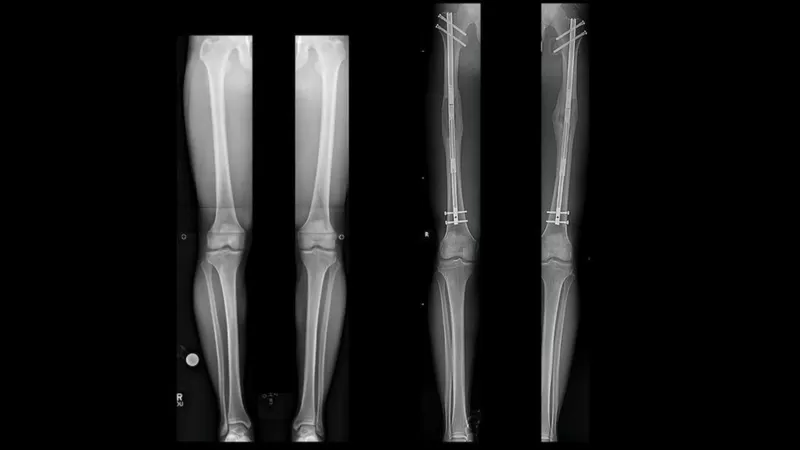

为了让罗圈腿变直少女遭受8处断骨之痛医生早矫正不用遭那么多罪

图片尺寸1080x1440